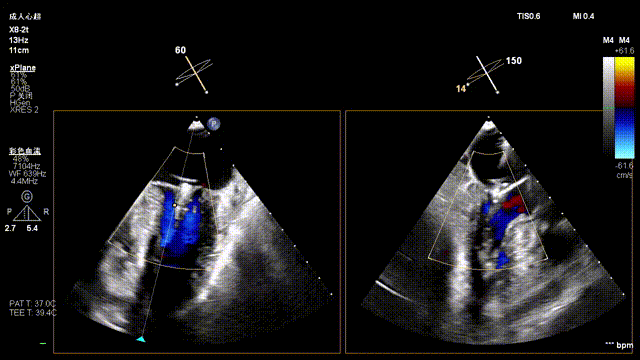

Mitral Valve Repair Stage: Via the transfemoral venous approach, a 4.0 cm atrial septal puncture was performed, and one mitral valve clip was selected. The unique feature of wide-angle deployment effectively resolved the issue of excessive leaflet tension during valve clip closure. Under the precise guidance of ultrasound, one clip was successfully implanted at the site of the widest regurgitation in the A2-P2 segment of the mitral valve. Immediate postoperative TEE assessment showed that mitral regurgitation was reduced to trivial (1+), the mean transvalvular pressure gradient was only 3 mmHg, and pulmonary venous retrograde flow was significantly improved.

Mitral regurgitation

3D color Doppler

Color Doppler of Mitral valve Zone 2